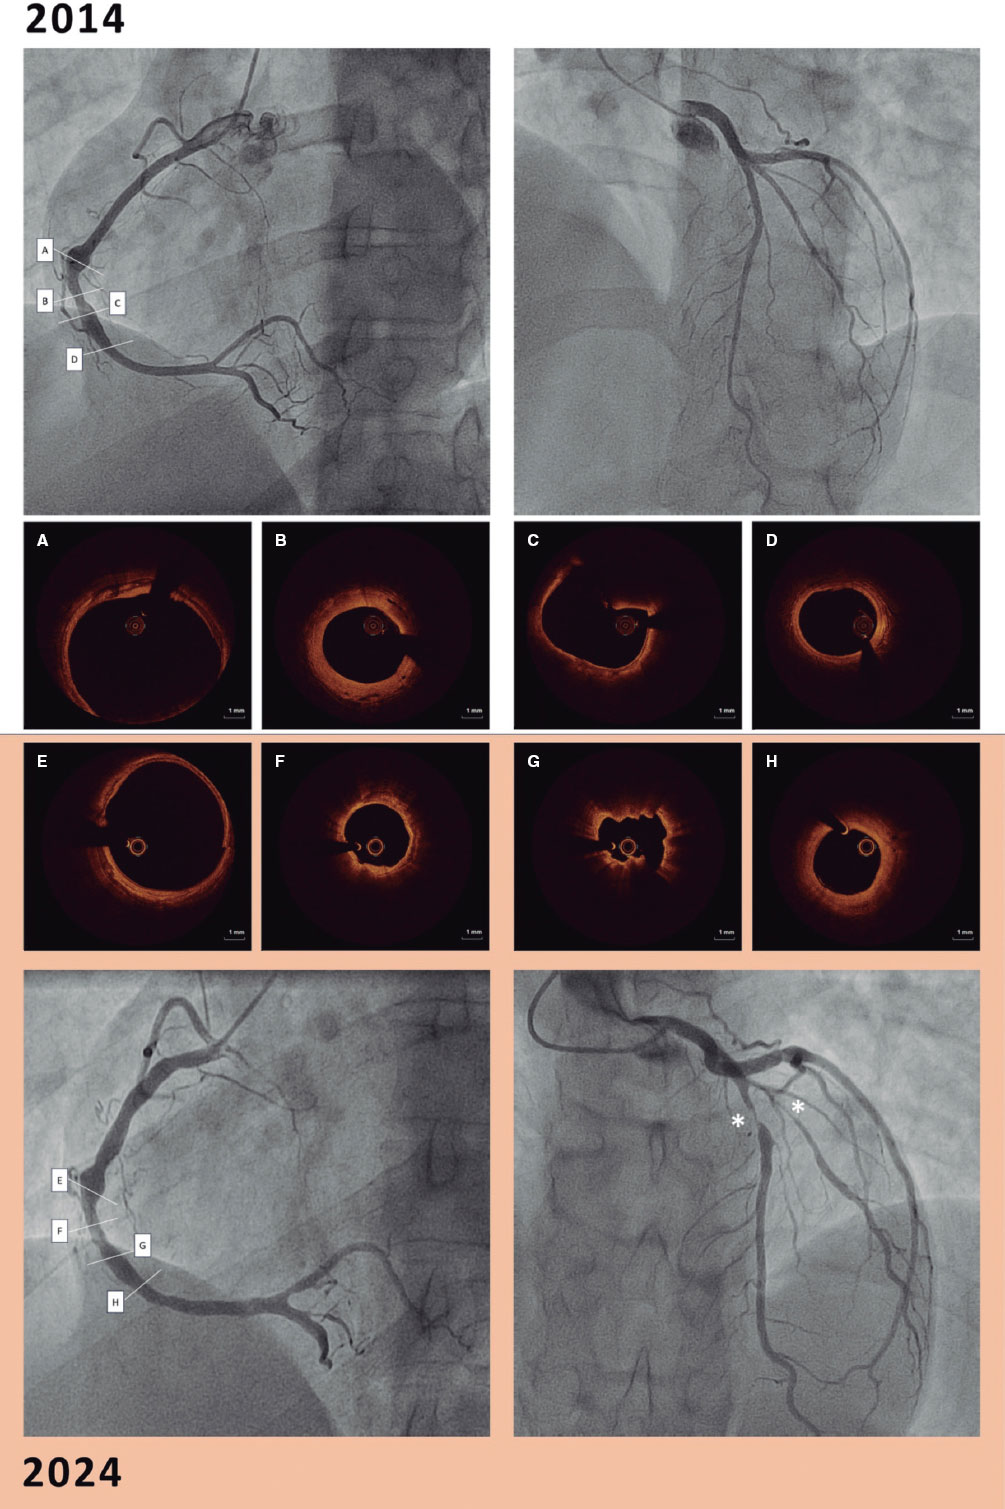

In 2014, a 25-years-old male with a past medical history of hypereosinophilic syndrome was referred to our center after an incidental finding of right coronary artery calcification on a computed tomography scan. A coronary angiography revealed the presence of aneurysmal lesions in the right coronary artery (RCA) (figure 1). OCT imaging showed mixed arterial wall abnormalities: a calcified aneurysm (figure 1A), fibrotic intimal thickening with medial disruption and prominent vasa vasorum (figure 1B), calcification (figure 1C), and a less diseased distal vessel (figure 1D). Treatment with acetylsalicylic acid 100 mg daily was initiated.

Figure 1.

In 2024, repeat coronary angiography for exertional angina showed RCA disease progression with larger mid-RCA calcification, confirmed by OCT of the same artery segment. Furthermore, the distal segment showed disease progression with intima thickening and medial disruption (figure 1; figure 1E-1H). A new critical stenosis was found in the left anterior descending coronary artery. Furthermore, a biopsy was obtained from an aneurysmal segment of the temporal artery (figure 2). Histopathological findings were similar to those seen on the OCT of coronary arteries. The thickened arterial wall was characterized by fibrous/myofibroblastic intimal hyperplasia, acute inflammatory infiltrate, necrosis, and fibrinoid changes (figure 2A-arrow). Moreover, a loss of the internal elastic lamina (figure 2B-arrow and figure 2A- asterisk) and adventitial vessels confirmed the presence of perivascular chronic inflammation.